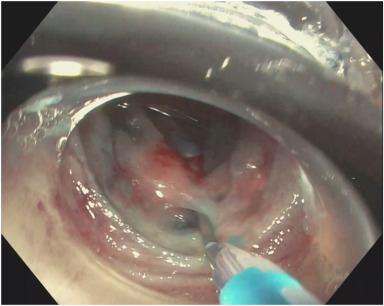

🔎 JNET 2A lesion.

Do you see it?

🔴 Barley visible central slit → pit.

🔵White marginal epithelium around it.

🟢Dark microvascular network.

Optical diagnosis isn’t guesswork - it’s systematic.

Learn a structured approach to lesion characterization.

opticaldx.com